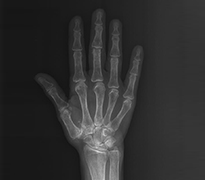

El ve kol eklemlerinde kireçlenme, eklem yüzeyini oluşturan kıkırdak yapının zamanla bozulmasıyla ortaya çıkan dejeneratif bir durumdur. En sık parmak eklemlerinde, başparmak kökünde ve el bileğinde görülür. Hastalarda ağrı, hareket sırasında hassasiyet, tutukluk ve zamanla şekil değişiklikleri gelişebilir. Kavrama gücünde azalma ve ince işlerde zorlanma da sık karşılaşılan şikayetler arasındadır. Bu durum sadece yaşa bağlı değil, travmalar sonrasında da gelişebilir. Özellikle skafoid kırığı sonrası uygun tedavi edilmezse el bileğinde zamanla kireçlenme ortaya çıkabilir.

Parmak Eklemlerinde Kireçlenmeler

Başparmak Kök Eklem Kireçlenmesi (1.cmc Eklem Artrozu)